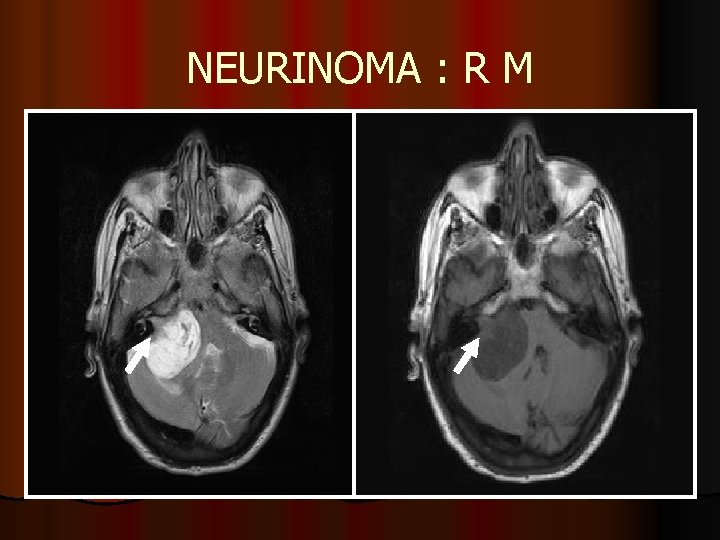

NEURINOMA l No malignizan l Afectación bilateral estatoacústico ( NF II ) l Captación intensa de contraste l El componente cisternal suele ser mayor que el intracanalicular l Puede producir cambios de edema en el tronco cerebral por efecto masa

NEURINOMA : R M